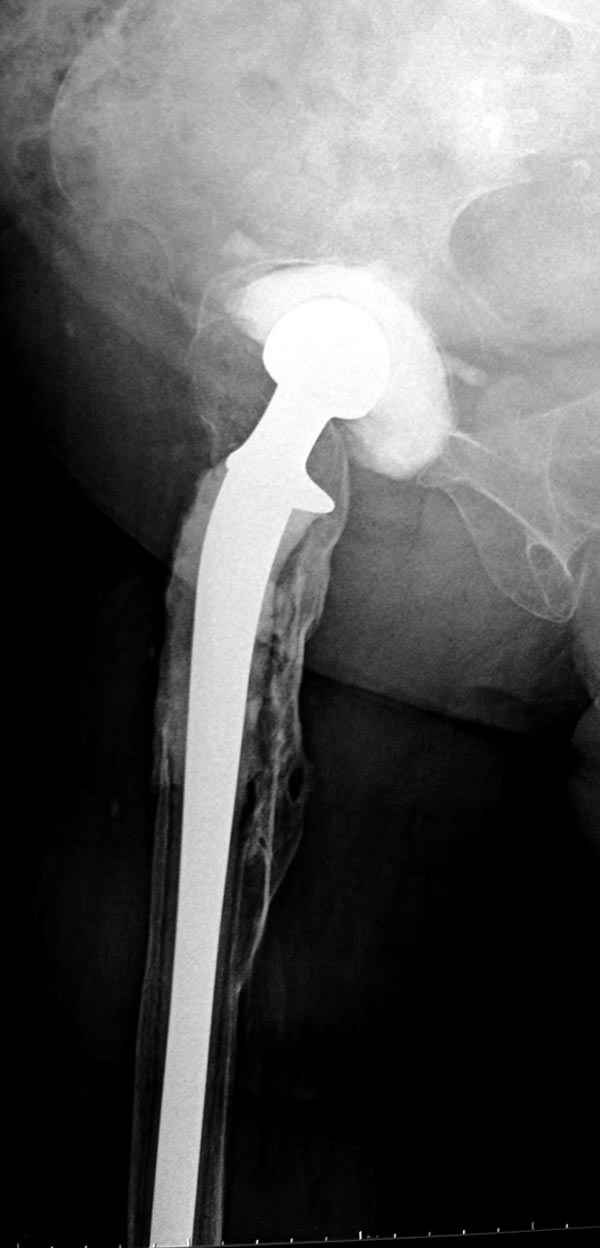

Больному выполнено тотальное эндопортезирование левого ТБС имплантатом Aesculap 05.02.07. В анамнезе в 1988 году травма при ДТП, оперирован в г.Москва - производился синтез заднего края шурупами с аутопластикой. После произведенного эндопортезирования, через 3 нед после операции у больного открылся свищ в области послеоперационного рубца с прозрачным отделяемым желтоватого цвета. Болей и повышения температуры не было. При посеве выявлен Enterococcus faecalis - умеренный рост. Больному было выполнено иссечение свищевого хода (доходил до зоны эндопротиеза), дренирование. Промывался в течение 12 дней растворами антисептиков. Швы сняты на 14 сутки после операции. В тот же день вновь открылся свищ на прежнем месте. Болей и температуры нет. В настоящее время я промываю свищевой ход раствором йодопирона - динамика слабоположительная (объем полости не уменьшается, однако отделяемого практически нет). Протез стабилен. Больной активен. Ходит с костылем. Болевого синдрома нет. Что подскажете? Бился ли кто с такой тварью как Enterococcus faecalis? И кто кого победил? Заранее Всем признателен за советы!!!

Так что вместе ожидания, можно было бы рассмотреть предлагаемый вариант, потом, если это возможно было бы интересно посмотреть на рентгенологическую картину.